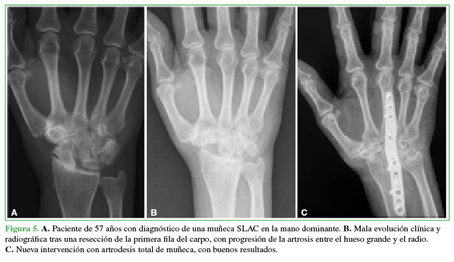

Se estudió la necesidad de otra intervención con una artrodesis total de muñeca por mala evolución clínica. El 12,12% (4 casos) requirió una nueva operación, eran pacientes con SNAC/SLAC II y una lesión condral en el hueso grande detectada durante la cirugía (Figura 5). El tiempo medio hasta la artrodesis fue de 16.5 meses (rango 10-22).

Hubo una correlación inversa entre el grado de artrosis radiocarpiana preoperatoria y el resultado obtenido según la EAV (p <0,03), los peores resultados clínicos ocurrieron en los pacientes con una lesión condral en el hueso grande, detectada durante la cirugía, quienes requirieron una nueva operación con artrodesis total de muñeca.

El 12,12% de nuestra muestra necesitó otra intervención, una artrodesis total de muñeca por mala evolución clínica, dato que se corresponde con los publicados en otros estudios, donde se describe una tasa de reconversión a artrodesis radiocarpiana de entre el 4,9% y el 15%.3,7,16Se corresponden con lesiones diagnosticadas como SNAC/ SLAC II, en las que se detectó una lesión condral en el hueso grande, durante la cirugía, lo cual nos hace pensar que el uso de esta técnica en pacientes con mayor grado de degeneración articular antes de la cirugía puede llevar a un peor resultado operatorio. Consideramos que el extenso tiempo desde el diagnóstico y la inclusión de los pacientes en la lista de espera quirúrgica hasta el día de la cirugía (media 2 años) ha podido influir en los hallazgos intraoperatorios de lesión condral en el hueso grande.